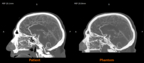

RadioMatrix is the first and only 3D printing material that enables precise control of radiopacity – allowing users to produce patient-specific models with repeatable, consistent, and fully tunable visibility on X-ray based imaging. Stratasys developed RadioMatrix to support a new era of medical imaging. Its unmatched fidelity for computed tomography (CT) phantoms was later underscored by research conducted with Siemens Healthineers, which validated RadioMatrix’s capabilities and accuracy for accelerating innovation in device testing, calibration, and education.

UK-based work with partners such as CPI and Beaumont Hospital is already demonstrating the impact of radiopaque 3D-printed models in practice, with radio-realistic cerebral angiography phantoms being used to improve the fidelity of imaging-based training and create more controlled, repeatable environments for research.

Early research from the Stratasys–Siemens Healthineers collaboration shows that 3D printed RadioMatrix™ phantoms can closely replicate real human tissue in CT imaging, with deviations reported as low as single Hounsfield units (HU) in critical areas such as grey matter and veins. By combining Stratasys’ Digital Anatomy™ 3D printing technology and radiopaque materials with advanced imaging algorithms, the partners are demonstrating anatomically realistic, radio-accurate phantoms that preserve fine anatomical details and pathological variations while offering a more consistent, ethical alternative to cadavers. These models are expected to improve how radiologists validate and optimize CT protocols and accelerate the development of new imaging algorithms for more precise diagnosis and treatment planning.